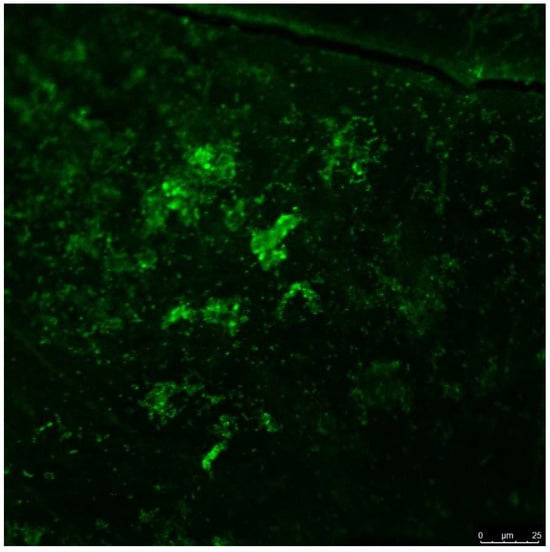

3.2. Qualitative Results of Scanning Electron Microscopy and Confocal Laser Scanning Microscopy